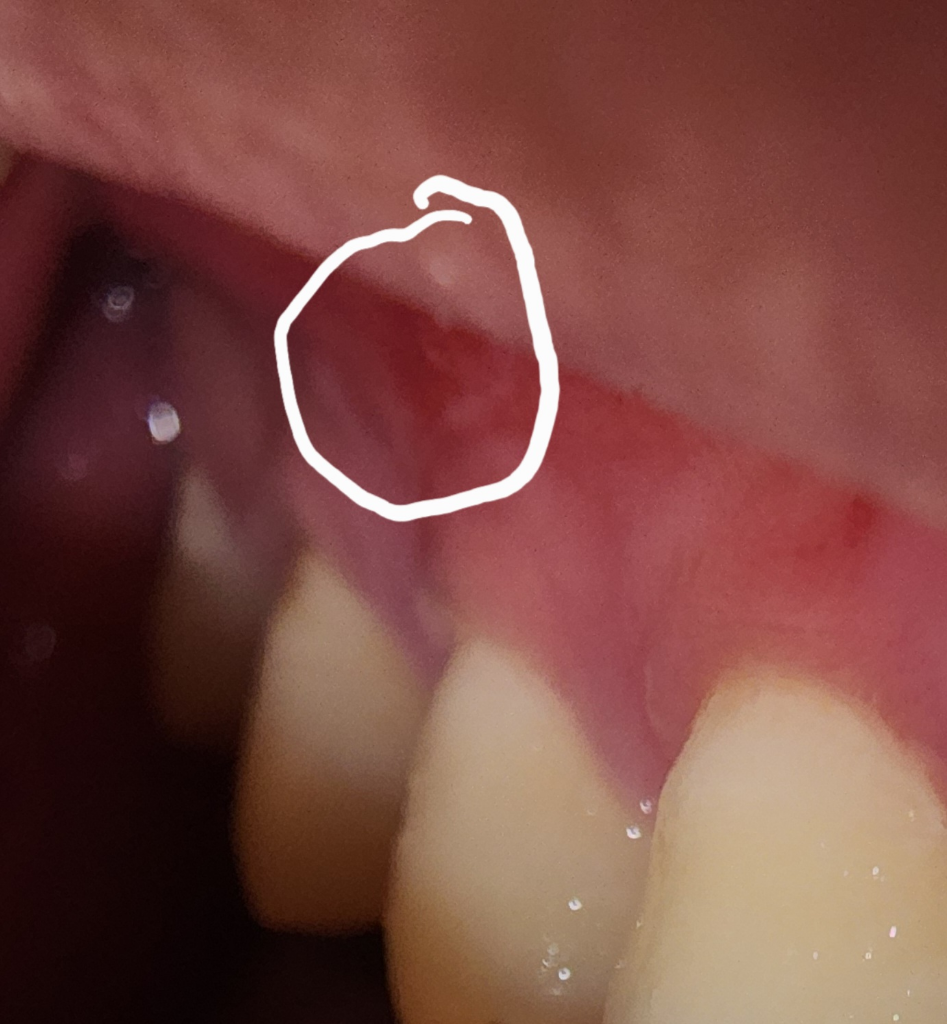

제가 잇몸을 쑤시다가 실수로 손이 미끄러져 손톱에

의해 상처가 길게 났습니다ㅠ 지혈은 된 상태이나

상처가 난 위쪽으로 빨갛게 되었는데 자연치유가 될까요? 패혈증으로 번지진 않겠죠?

사진상 육안으로 보기에 붓기 등의 감염증상은 확인되지 않습니다.

잇몸은 상처 회복이 빠르기 때문에 문제가 안될 가능성이 높지만 증상이 생긴다면 치과를 가보시는 게 좋겠습니다.

저정도 상처는 시간이 지나면 괜찮아 질꺼에요. 패혈증까지 걱정한 상처는 아니니 걱정하지마세요.

잇몸조직은 세포재생이 빠르게 일어나는 조직이기에 시간이 지나면 아물기에걱정하지 않아도 됩니다. 만약 걱정되는 경우에는 약국에서 판매되는 잇몸에 사용가능한 구내염 연고를 구매하여 사용하길 권합니다.

잇몸은 재생이 매우 잘되는 조직이기 때문에 상처가 나도 1주일이 지나면 대부분 회복이 됩니다.

불편감이 크다면 오라메디 등을 도포해 보세요.